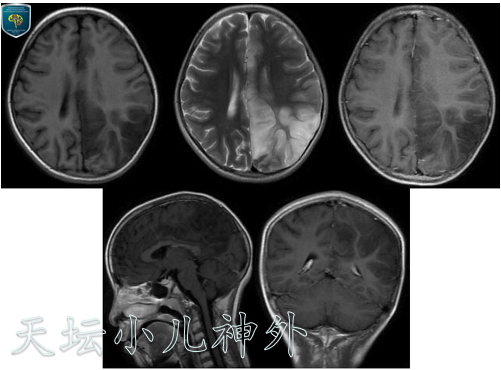

图1患儿2020年1月MR,可见病变弥漫,呈长T1长T2混杂信号,未见明显强化